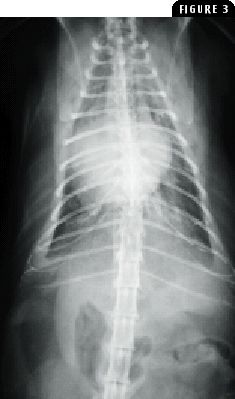

Thoracic trauma is common in dogs and may result in marked morbidity and mortality because of injury to the lung parenchyma (pulmonary contusion), pleural space (hemopneumothorax), great vessels, thoracic wall (rib fractures), diaphragm, or myocardium.